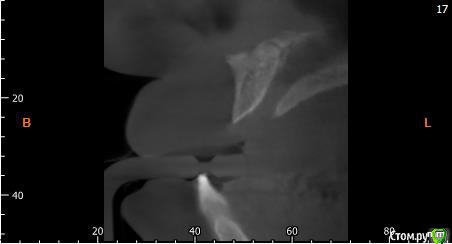

Собственно ситуация такая. Фронтальные зубы сверху были потеряны в результате серьезной травмы,  ! Фактически полное отсутствие костной ткани в области фронтальных зубов и по толщине и по высоте. Пациент ходит с чс протезом и хочет нечто несъемное.

Интересует как лучше это сделать при таких объемных дефектах.  Мои мысли первым этапом сосидж, потом 4 импланта. Но как быть с временным протезированием?